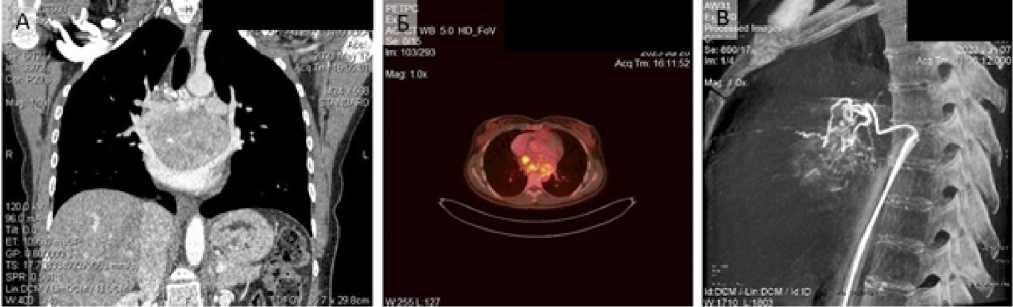

На втором этапе операции выполнен мультипортальный доступ справа. Начата мобилизация опухоли. Однако развилась десатурация до 75 %, которая потребовала перехода на двухлегочную вентиляцию и увеличения фракции кислорода во вдыхаемой смеси до 80 %. Заподозрена травма мембранозной части трахеи. Интраоперационно выполнена диагностическая фибробронхоскопия, травма исключена. Ввиду непереносимости однолегочной вентиляции продолжена двухлегочная ИВЛ, выполнена торакотомия справа. Произведено клипирование дренирующих опухоль вен в паратрахеальной области. При дальнейшей ревизии выявлена связь опухоли с задней стенкой левого предсердия (рис. 3). Для выполнения радикальной операции требовалась резекция левого предсердия в условиях искусственного кровообращения (ИК), что невозможно в условиях РНПЦ ОМР, в связи с чем операция была завершена. При манипуляциях с опухолью отмечались неоднократные подъемы артериального давления до 180/110 мм рт. ст и ЧСС до 120/мин, которые купировались в течение 5–10 мин. после прекращения манипуляций с опухолью.

Рис. 3. Инвазия опухоли в левое предсердие (интраоперационное фото)

Fig. 3. Tumor invasion into the left atrium (intraoperative photo)

На 3-и сутки после операции пациентка переведена в РНПЦ «Кардиология». Через 10 дней после первой операции совместной бригадой онко- и кардиохирургов в условиях ИК было выполнено удаление опухоли с резекцией и пластикой левого предсердия. Учитывая первичное выполнение частичной мобилизации опухоли из левосторонней ВАТС и правосторонней торакотомии, возможность подключения ИК различными способами, для выполнения операции был выбран доступ в виде правосторонней переднебоковой реторакотомии в 5-ом межреберье. Этот доступ также обеспечивает лучшую достижимость и практически полную визуализацию задней стенки ЛП, по сравнению со срединной стернотомией. Интраперикардиально и экстраперикардиально были мобилизованы легочные вены, правая легочная артерия, верхняя полая вена. Опухоль мобилизована от бифуркации трахеи, левого и правого главных бронхов с клипированием питающих сосудов диаметром до 2 мм. Затем стандартно был подключен АИК по схеме «правое предсердие — восходящая аорта». Операция выполнена в условиях нормотермической перфузии и кардиоплегии на основе крови. После остановки сердца устья правых легочных вен отсечены с площадкой ЛП, свободной от опухоли. Произведена резекция задней и верхней стенки левого предсердия с исходящей из нее опухолью с сохранением устьев левых легочных вен. Гиперваскуляризация опухоли, несмотря на предварительное клипирование основных питающих сосудов, потребовала дополнительного прошивания вен, дренирующих опухоль в проекции левого главного бронха. Для восстановления целостности левого предсердия было произведено его формирование «de novo» полотном ксеноперикарда крупного рогатого скота «Биокард» (СП ООО «Фармлэнд», РБ) обвивным непрерывным швом размером 5 × 6 см. Во вновь сформированном предсердии было выполнено отверстие 2 × 3 см, куда реимплантированы устья правых легочных вен. Самостоятельное восстановление сердечной деятельности после реперфузии. Длительность ишемии составила 134 мин., ИК — 190 мин. Пациентка экстубирована через 3 ч. после окончания операции, общий объем послеоперационной кровопотери в первые сутки составил 450 мл.

На 2 послеоперационные сутки диагностирована полисегментарная пневмония, которая разрешилась на 9 сут. Пациентка выписана на 10 сут. после операции. Объем левого предсердия и его функция адекватные, по результатам ЭХО-КГ и КТ-ангиографии (рис. 4).

Рис. 4. Вид после завершения реконструкции предсердия бычьим перикардом: А — интраоперационное фото; Б — КТА-ОГК после операции

Fig. 4. View after completion of atrial reconstruction with bovine pericardium: A — intraoperative photo; Б — postoperative thoracic CTA